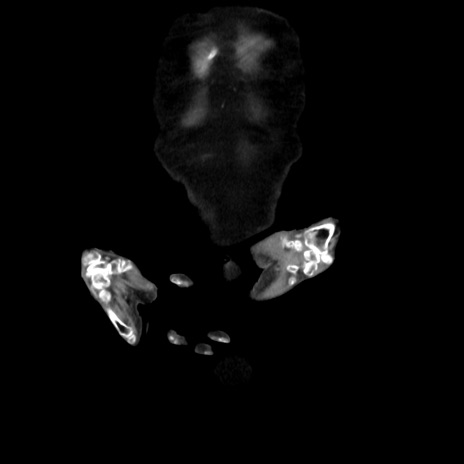

矢状断像